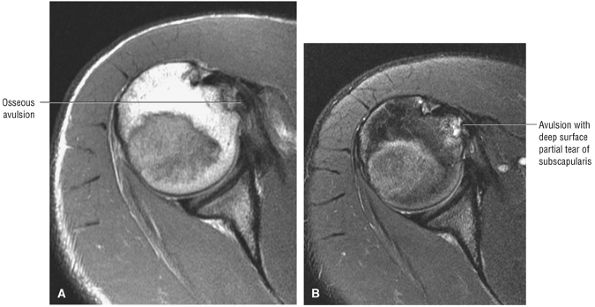

FIGURE 8.102 ● (A) The anterior undersurface of the acromion and the coracoacromial ligament form the coracoacromial arch. The subacromial subdeltoid bursa facilitates the passage of the rotator cuff and proximal humerus under the coracoacromial arch. (B) A superior axial image shows the anterior-to-posterior extent of the coracoacromial (CA) ligament perpendicular to the supraspinatus tendon. The fluid in the subacromial-subdeltoid bursa represents fluid between two serosal surfaces in contact with each other. One serosal surface is contributed by the undersurface of the coracoacromial arch and deltoid, and the other serosal surface is on the bursal side of the cuff.

|

![]() |

FIGURE 8.103 ● Pseudospur. The normal broad attachment of the coracoacromial ligament to the inferior surface of the acromion is shown on (A) T1-weighted coronal oblique and (B) sagittal oblique images. The low-signal-intensity acromial cortex (black arrows) and adjacent coracoacromial ligament and lateral slip of the deltoid attachment (white arrows) give the false impression of a small subacromial spur in the coronal plane. This pseudospur should not be misinterpreted as impingement; otherwise, unnecessary acromioplasties may be performed on patients with a normal coracoacromial ligament attachment and no associated acromial spurs.